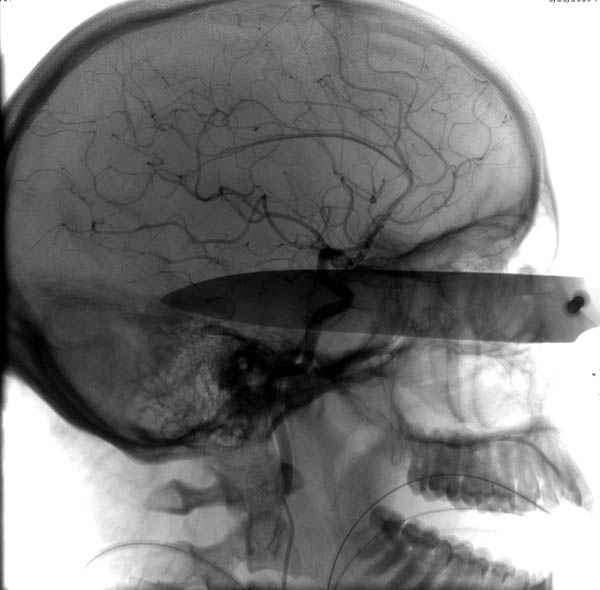

В своих выступлениях я рассказывал, что наши центры в мирное время по пенетрирующим травмам не уступает Ираку или Афганстану, и вот недавно к нам поступила больная 22 лет, травма "ножом в глаз" от бывшей подруги нынешнего "бой френда".

При поступлении в сознании, жаловалась на неприятные ощущения в глазнице.

По протоколу сделаны все необходимые исследования: рентген, ангиограмма с 3Д реконструкцией, где обнаружили что все жизненно важные сосуды не задеты, даже некоторые "сидят" изгибаясь на ноже.

Одним махом нож удалить не удалось, пришлось раскачать и потом двумя руками удалили нож. Рана без кровотечения, обработана и зашита.